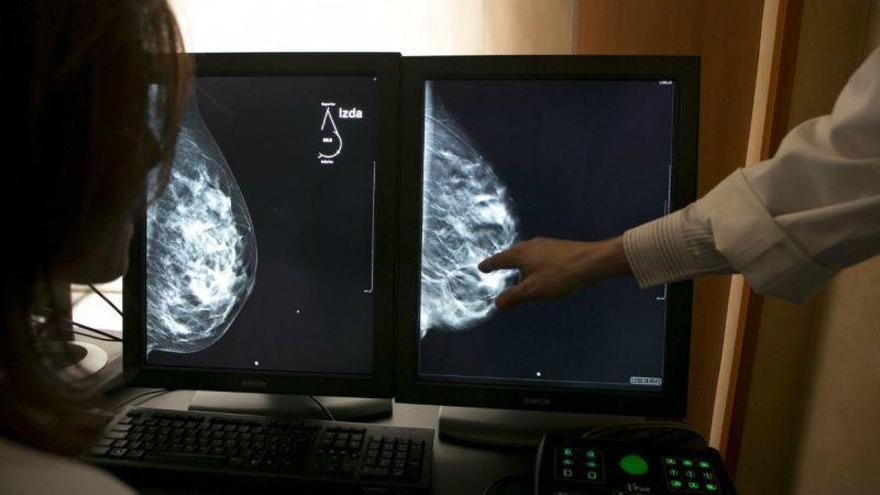

En una nota, el sindicato señala que se suma, un año más, a las distintas campañas e iniciativas informativas y de sensibilización social puestas en marcha a nivel internacional (Organización Mundial de la Salud) y nacional (Asociación Española Contra el Cáncer) «para que las administraciones públicas, profesionales sanitarios y ciudadanos sigan trabajando de forma conjunta para reducir lo máximo posible la incidencia de esta enfermedad». En esta ocasión, la organización sindical ha querido poner el acento en la importancia de la detección precoz de la enfermedad, así como en la prevención y fomento de conductas y hábitos de vida saludables entre los ciudadanos. Unos ámbitos de actuación en los que la labor de las enfermeras y enfermeros resulta fundamental, añade.

En este sentido, el sindicato de Enfermería pone especial énfasis «en la necesidad de reorientar las políticas sanitarias de nuestro país y destinar más recursos humanos y materiales a la prevención de la enfermedad, ya que sigue siendo la gran asignatura pendiente del Sistema Nacional de Salud». Satse recuerda que los últimos datos apuntan a un aumento en los últimos años de los casos.